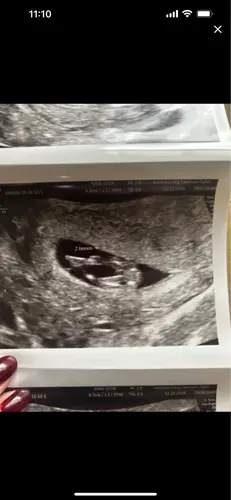

Baby 1, wat zou t worden?

Baby 1 🩵